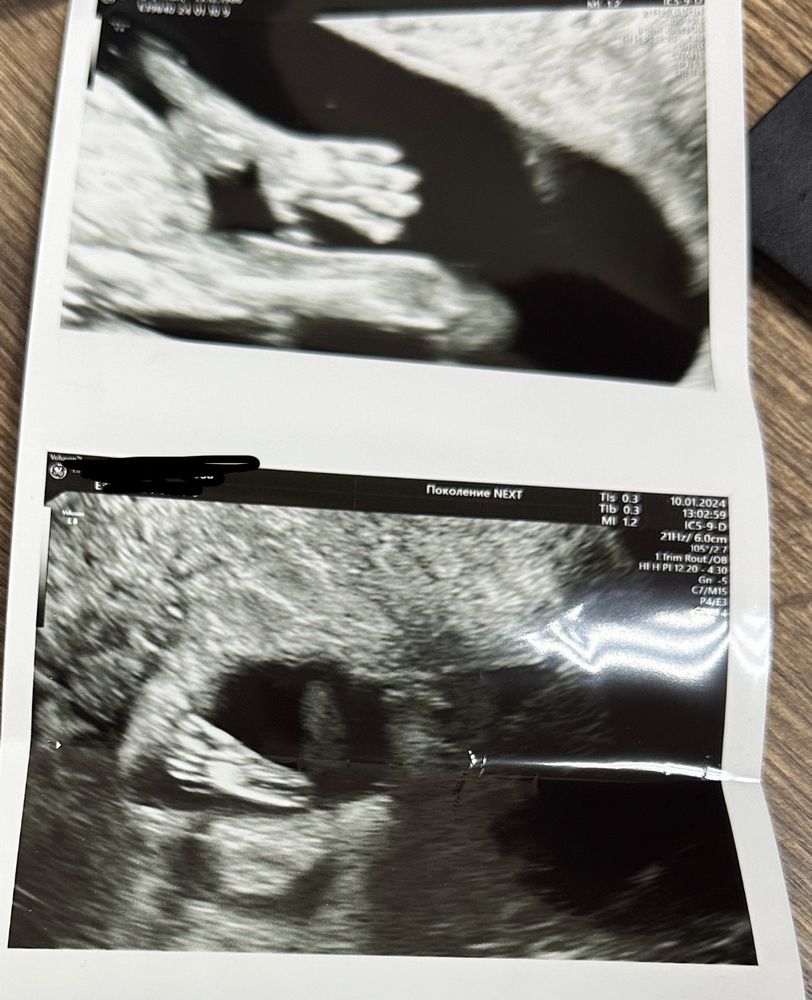

Нам 13 недель ❤️ фото ручки и ножки разбили мое сердечко ❤️

А мне не делали таких фото на 14 недель, и пол даже не смогли определить толком. Сказали рано еще. Надеюсь в 16 недель увидят пол ребенка. Клиника платная у нас, аппарат УЗИ хороший Изображение Только так сфоткали

Лучшие снимки с УЗИ, что я видела))) Вот это красиво врач подловил)))

Цыпочка, дааа) это моя любимая Бойкова (принимает в Кулакова и Поколение Некст).